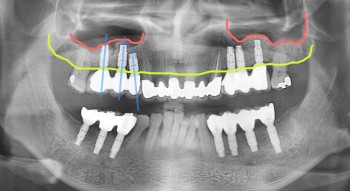

고난이도 임플란트 수술 전문의에게 맡기세요!

무치악 임플란트 치료로 잃어버린 치아를 되찾아...

네비게이션 임플란트 시술